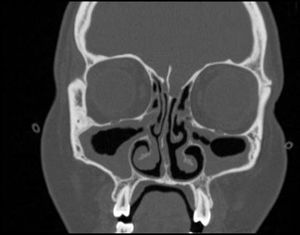

Femenino de 18 años con antecedente de asma de difícil control, sinusitis recurrente y enfermedad pulmonar intersticial diagnosticada en febrero de 2021, inicia padecimiento actual en enero de 2022 con tos, sibilancias y disnea. A la exploración física inicial destacan estertores bilaterales, dermatosis localizada en el dorso de ambas manos caracterizada por máculas eritemato-violáceas pruriginosas, las cuales no blanquean a la digitopresión. Los laboratorios de ingreso presentan leucocitosis de 15,4×109/l, con eosinofilia del 45%, así como elevación de reactantes de fase aguda (PCR y VSG). La tomografía de senos paranasales demuestra hipertrofia parasinusal, sinusitis crónica. La tomografía de tórax sin contraste demuestra imágenes de vidrio deslustrado multilobares que afectan más del 50% del parénquima pulmonar. Se realiza broncoscopia, se descartan causas infecciosas y se demuestran células inflamatorias con predominio eosinofílico. La biopsia nasal demostró infiltrado inflamatorio eosinofílico sin granulomas. Los estudios histopatológicos contra el citoplasma neutrofílico fueron negativos. Se realizó diagnóstico de granulomatosis eosinofílica con poliangeítis, se inició tratamiento con glucocorticoides a dosis altas con mejoría de las lesiones pulmonares y cutáneas. La paciente egresó con tratamiento a base de reducción gradual de glucocorticoides (descritas en el protocolo PEXIVAS), metrotexato 15mg a la semana y mepolizumab 100mg subcutáneo mensual. Después de 24meses de tratamiento se ha logrado la remisión total de la sintomatología, y el control bioquímico muestra menos del 1% de eosinófilos, con normalización de reactantes de fase aguda y puntaje en la escala Birmingham Vasculitis Activity Score (BVAS) de 0. La paciente no ha presentado ningún efecto adverso en el curso de su tratamiento.

La granulomatosis eosinofílica con poliangeítis (EGPA) es una enfermedad inmunomediada poco frecuente. Las características principales son asma de inicio tardío, eosinofilia periférica y tisular1. El estándar de oro diagnóstico es la biopsia con evidencia de infiltrados eosinofílicos y necrosis fibrinoide. La piedra angular del tratamiento son los glucocorticoides2. Sin embargo, los tratamientos biológicos, como el mepolizumab, un anticuerpo monoclonal humanizado contra el receptor de IL-5, se ha demostrado como un tratamiento eficaz para EGPA3. Los criterios de clasificación recientemente actualizados respaldan el diagnóstico en este caso y evitan retrasos en el tratamiento1. Aunque la dosis recomendada de mepolizumab suele ser de 300mg mensuales, se trata de un medicamento de alto coste4. Por lo tanto, en este caso decidimos inicialmente utilizar metotrexato, prednisona y dosis bajas de mepolizumab, con un resultado favorable4,5 (figs. 1 y 2).